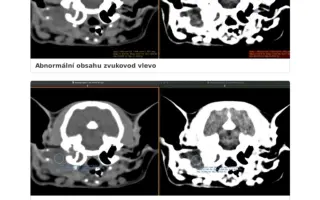

Laruška má úspešne po CT vyšetrení a operácii oboch zvukovodov !

Milí ľudia, medzičasom, v procese schvaľovania na Doniu, moja milovaná Larunka už absolvovala CT a následne do týždňa aj operáciu na klinike Vet point – AniCura u skvelého MVDr. Valáška. Už sme viac nemohli čakať. Larunke sa musel odstrániť celý pravý zvukovod aj abces, ktorý z necho vyrastal a tvoril sa stále horšie donekonečna a naviac sa odstránil aj polyp v ľavom zvukovode, o ktorom sme predtým nevedeli, ale na CT sa ukazovalo niečo, čo bolo potrebné u operácie skontrolovať a bol to nakoniec polyp. Peniažky, ktoré som musela vyplatiť na CT a operáciu musím splatiť najneskor do 1 - 2 mesiacov. CT ma stálo 450,- operácia 900,- Eur a samozrejme liečba, kontroly atď nie sú u konca. Prikladám medzi fotky aj účty, bohužiaľ takto sekane, po viac stranách, neviem to sem inak nahrať v celku, aby to bolo čitateľné. Vopred ďakujem každému za podporu čiastkou, akou môžete a chcete nám pomôcť aj za každé zdieľanie či dobrú energiu poslanú naším smerom:). S láskou najšťastnejšia mačacia mamina Evi, že to máme konečne za sebou a Larunka, najstatočnejší pacient. Ešte je pred nami cesta, ale verím, že už to bude stále lepšie, a dúfam, že aj finančne sa mi podarí to prežiť s vašou pomocou. Ďakujem zo srdca aj Doniu za možnosť a pomoc so zbierkou.

Odvtedy ju trápia vážne chronické problémy s pravým uškom – opakované zápaly, polypy, abscesy a opuchy lymfatických uzlín. Podstúpila viacero vyšetrení a zákrokov, brala antibiotiká, kortikoidy, homeopatiká aj alternatívnu liečbu. Pomohlo to len dočasne.

Momentálne je situácia kritická – uško je nepriechodné, zápaly sa vracajú a hrozí, že infekcia sa rozšíri ďalej. Veterinári odporúčajú CT alebo MRI vyšetrenie a pravdepodobne operáciu zvukovodu (abláciu).